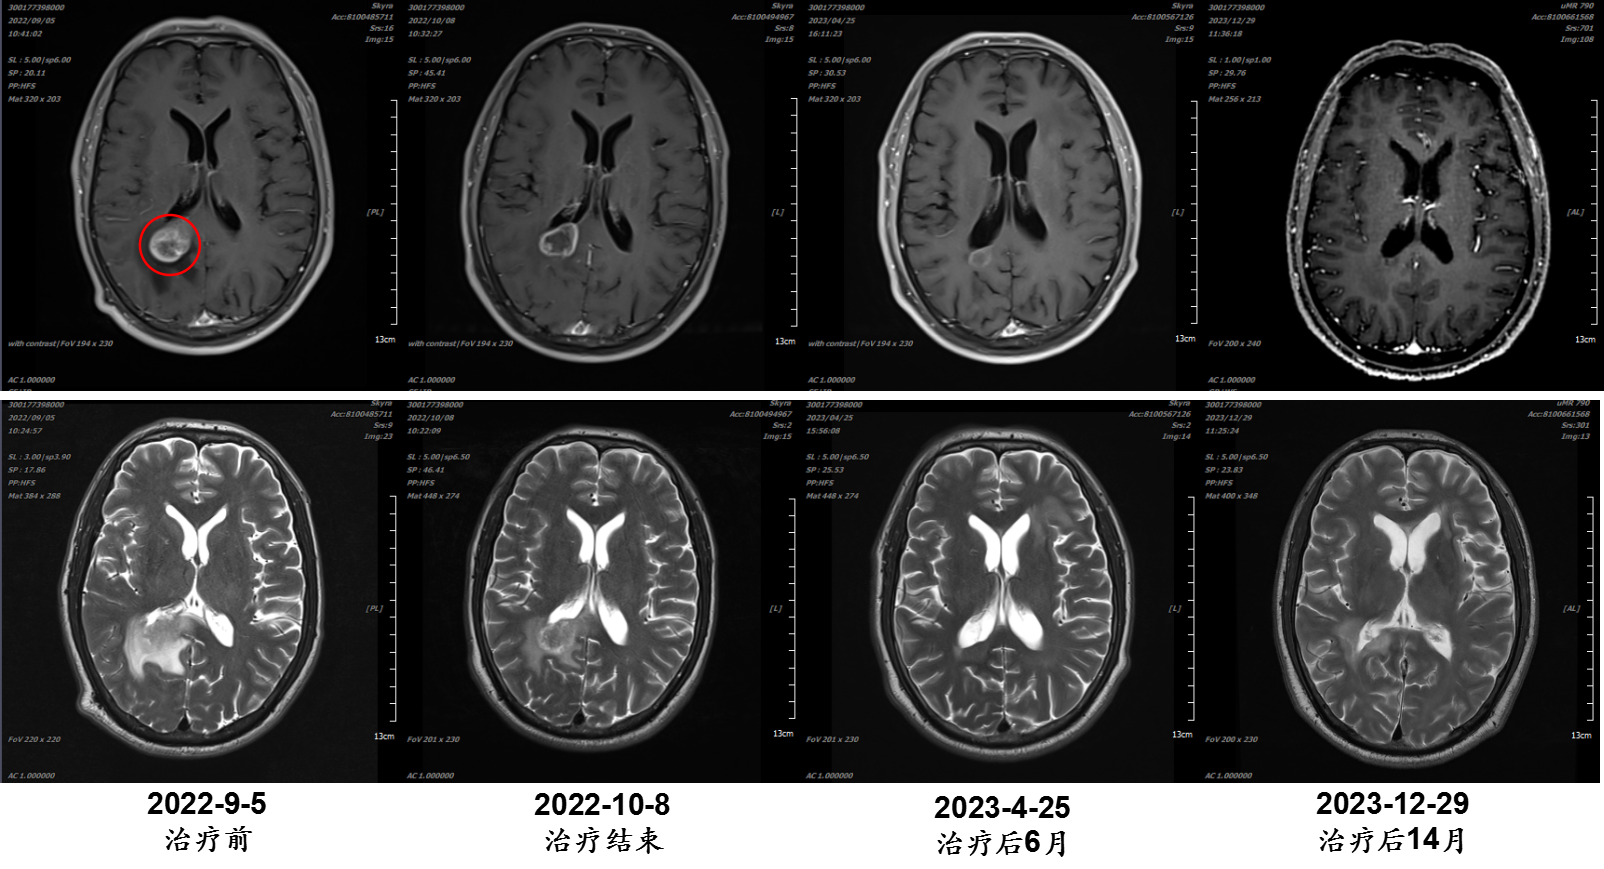

张某某,男,57岁;诊断:食管癌多发脑转移;治疗时间:2022/9/20至2022/10/7。

病例提供医生:王馨 科室:放疗中心一科(国际一部)